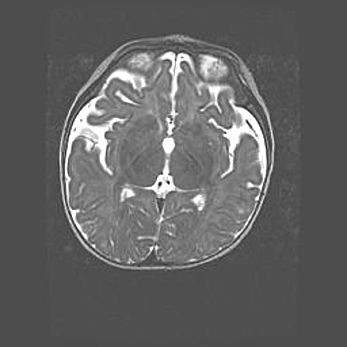

Наружная гидроцефалия с возможной атрофией височных областей.

Возраст: 28 дней

Вес: 3670 г

Пол: мужской

Окружность головы: 38 см

Срок гестации: 40 недель

Гидроцефалия головного мозга у новорожденных – это заболевание, которое характеризуется скоплением избыточного количества спинномозговой жидкости в желудочковой системе головного мозга в результате затруднения её перемещения от места выработки к месту поглощения в кровеносную систему или вследствие нарушения абсорбции. При открытой наружной форме гидроцефалии у новорожденных расширяются и переполняются субарахноидные пространства.

При нормотензивных  формах,  которые,  как  правило,  являются  следствием  перенесенных ишемических  повреждений  паренхимы  мозга,  возможно  сочетание микроцефалии  с нормотензивной гидроцефалией. В основе данных изменений лежит атрофия больших полушарий с преимущественной  локализацией  в  лобно-височных  областях.